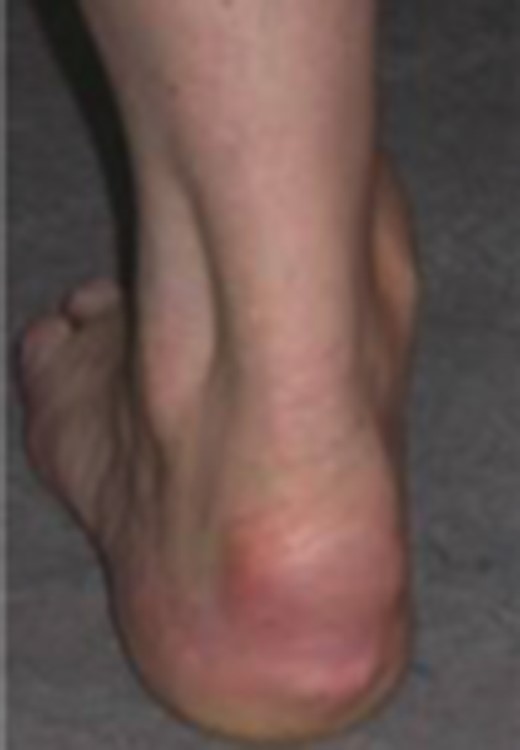

On examination, there was thickening and localized tenderness over the left subcutaneous bursa and a slightly widened heel profile. The distal Achilles was thickened. There was no tenderness or swelling in the region of the retrocalcaneal bursa, nor any thickening or tenderness over the tendon midportion.

Dynamic ultrasound examination of the left heel showed a diffusely thickened subcutaneous bursa, with fluid-rich islands. Regions of high blood flow were seen in the bursal walls. There was tendinopathy in the distal Achilles, which measured 6–7 mm in thickness with intra-tendinous bone formations and calcification, but no high blood flow. Finally, there was a minor Haglund-like deformity with a sharp edge and a slightly enlarged retrocalcaneal bursa with the appearances of scar tissue formation, but no fluid or increased blood flow. There were no signs of partial ruptures in the distal part of the Achilles. These ultrasound findings were consistent with those of a previous MRI (Figs 1–5).

Ultrasound image of thickened subcutaneous bursa and bone formations in the distal Achilles.